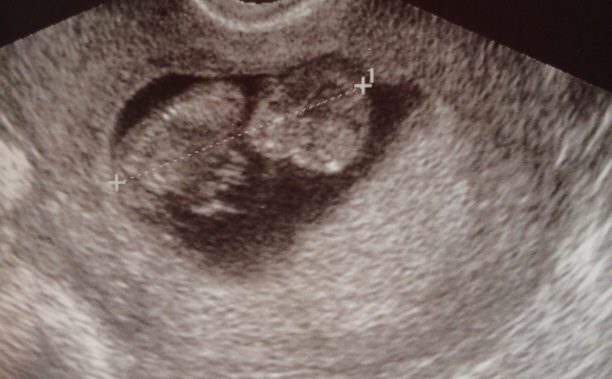

Well ladies I think it's safe to say baby has made a happy home for 7-8 more months. I will be 11 weeks tomorrow. So excited to say baby looks awesome! He/she is was waving at me and dancing all over the place. I got to see a straight spin along with hands and feet. He/she so far looks to have long legs like mommy.

Baby also had a heartbeat of 163 and measuring right on track. I go back in on May 20th which seems so far away! But 3-4 weeks after that we get to go in for a early anatomy scan to make sure baby is developing right and of course find out what we are having.